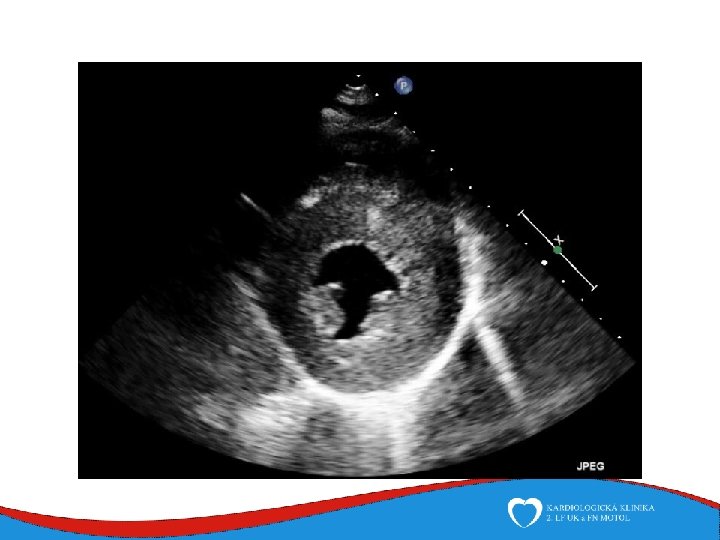

Diagnosis Family history Phisical examination ECG systolic murmur at the apex and lower left sternal border heterogenous LVH, patol. Q , QS, …. ECHO – golden standard MRI septal thickness more than 15 mm, papillary muscles hypertrophy, mitral anterior leaflet elongation, pressure gradient regions of myocarrdial fibrosis regions of late gadolinium enhancement (LGE) Stress test blood pressure responce ECG monitoring ventricular arrhythmia Selective coronarography

Left ventricular non-compaction Rare (cca 1: 7000) Primary genetic disease - Sarcomeric and mitochondrial genes ECHO Non-compacted myocardium especially in the apical part of the left ventricle

Left ventricular non-compaction • Signs and symptoms • Heart failure • Thromboembolic complications • LV trabecularization- predisposition • Anticoagulation therapy (systolic dysfunction) • DG – echo, MRI • Therapy – heart failure therapy, anticoagulation therapy

ECHO – anterior wall akinesis, LV EF 35%, mild mitral regurgitation, no dilation of right-sided chambers, no pericardial effusion